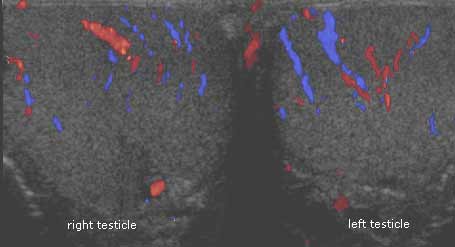

Ultrasonido de ambos testículos; el color muestra la circulación de la sangre. Vista desde los pies del paciente hacia la cabeza.

Nota: Las imágenes se muestra para fines ilustrativos. No trate de sacar conclusiones comparando esta imagen con otras en el sitio. Solamente los radiólogos calificados deben interpretar las imágenes.